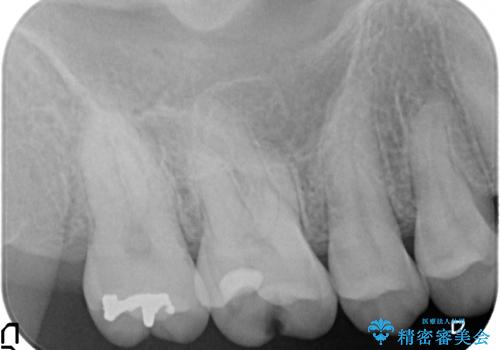

- 古い銀歯をセラミックで治療したいといらっしゃった方の症例です。

銀歯及び虫歯を除去後、セラミックインレーによる修復を行いました。